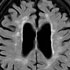

Forensic radiology represents the intersection of diagnostic imaging and legal medicine, playing an increasingly vital role in modern medicolegal investigations.